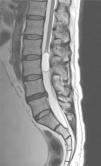

Case reportA male patient of 54 years of age was admitted to our hospital with 10 months’ evolution of lumbago with pain radiating to both lower extremities. In the last two months, his symptoms had gradually progressed with paraesthesia and saddle hypoesthesia, urinary incontinence and constipation. He reported no history of trauma or other spinal procedures. The neurological examination revealed cauda equina syndrome, urinary incontinence, loss of anal sphincter tone, paraesthesia of the lower extremities with a strength of 3/5 bilaterally and both proximally and distally, and bilateral patellar and achilles hyporeflexia. Magnetic Resonance Imaging (MRI) showed hyperintensity at the L2-L3 level in the T2 sagittal image (Fig. 1), while the axial image showed the same intraspinal, intradural and intramedullary feature to be heterogeneous, with the major component located centrally and a hypointense periphery (Fig. 2). It was decided to perform laminoplasty of L2 to L4, opening the dura mater, whereupon we observed that the major component was a central cystic lesion of friable, yellow-grey tissue. Consequently, the tumour was resected in its entirety. The histological examination revealed a mature teratoma with fully differentiated components (Figs. 3–6).

Images of the tumours obtained by Magnetic Resonance Imaging (MRI) guide the diagnosis of spinal teratoma.15 The morphological appearance on the MRI varies based on the location of the tumours. Intradural teratomas are often oval or lobulated heterogeneous masses, while extradural teratomas are more commonly found to have a “dumbbell” shape.5,6,15 Cases of extradural teratoma are frequently accompanied by malformation of the vertebral body, while intradural teratomas in adults are usually found under the dura mater, rarely invading the dura mater or vertebral body.3

ConclusionIntradural spinal teratomas are very rare, even more so in adults. The heterogeneous signal shown by MRI images can indicate the solid or cystic composition of the tumour lesion, which is extremely helpful for an early diagnosis of teratoma. The clinical picture is very non-specific, suggesting only compression of the spinal cord and/or medullary syndromes that could be caused by any other tumour lesion. Good outcomes are achieved with total surgical resection, as the clinical symptoms are caused primarily by compression of the spinal cord by the spinal teratoma. Extreme care is essential when resecting the tumour, in order to avoid breaking the cyst and disseminating its contents or post-surgical infections. Genetics is of little help, as there are no pathognomonic studies of this disease, and, as always with surgery, using histopathology to corroborate the result gives the most certain diagnosis.